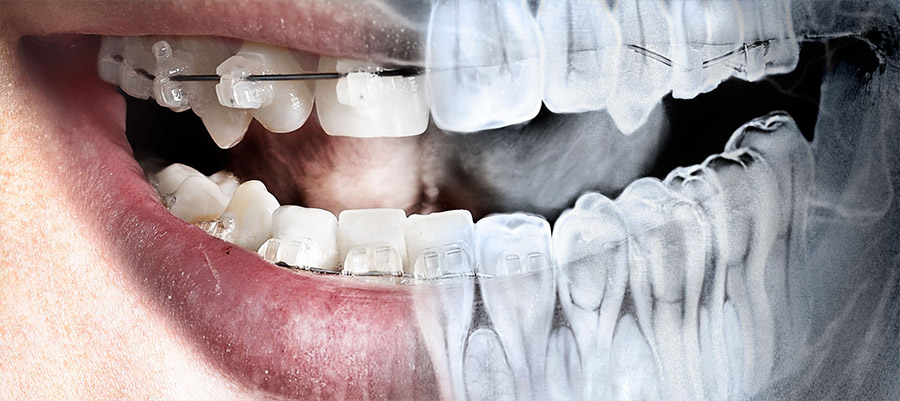

Цифровые технологии также революционизируют ортодонтию. С помощью интраоральных сканеров и специального программного обеспечения стоматологи могут создавать трехмерные модели челюстей пациента и планировать ортодонтическое лечение с высокой точностью. Это позволяет создавать индивидуальные брекет-системы и алигнеры‚ которые обеспечивают более эффективное и комфортное лечение.

Кроме того‚ цифровые технологии позволяют следить за прогрессом лечения в динамике‚ анализируя изменения в положении зубов и корректируя план лечения при необходимости. Это позволяет добиться более предсказуемых результатов и уменьшить риски осложнений.